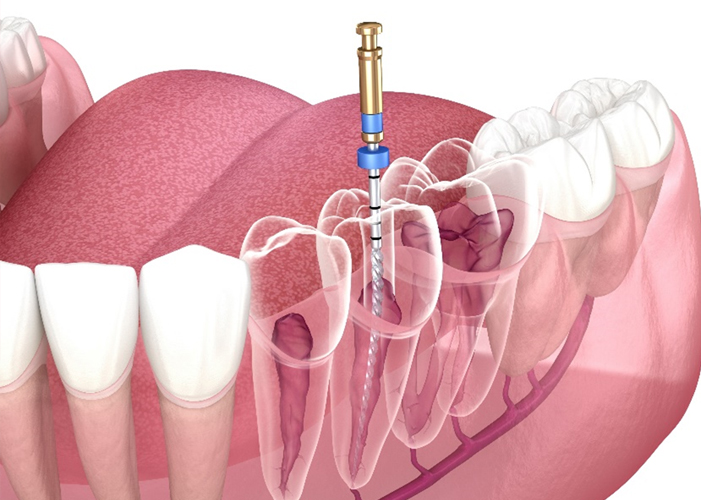

02

디지털 진단과 전문의의 손끝이 만나는 순간,

치료의 정교함이 달라집니다.

성공적인 임플란트 식립을 위해서는 정밀한 진단이 필수적입니다. 3D 스캔·CT·CAD/CAM 기반의 디지털 분석으로 오차를 줄이고, 통합치의학과 전문의 대표원장이 직접 진단·설계·최종 보철까지 전 과정을 담당하여 심미적인 조화와 기능적 안정성을 동시에 고려한 임플란트를 제공합니다.